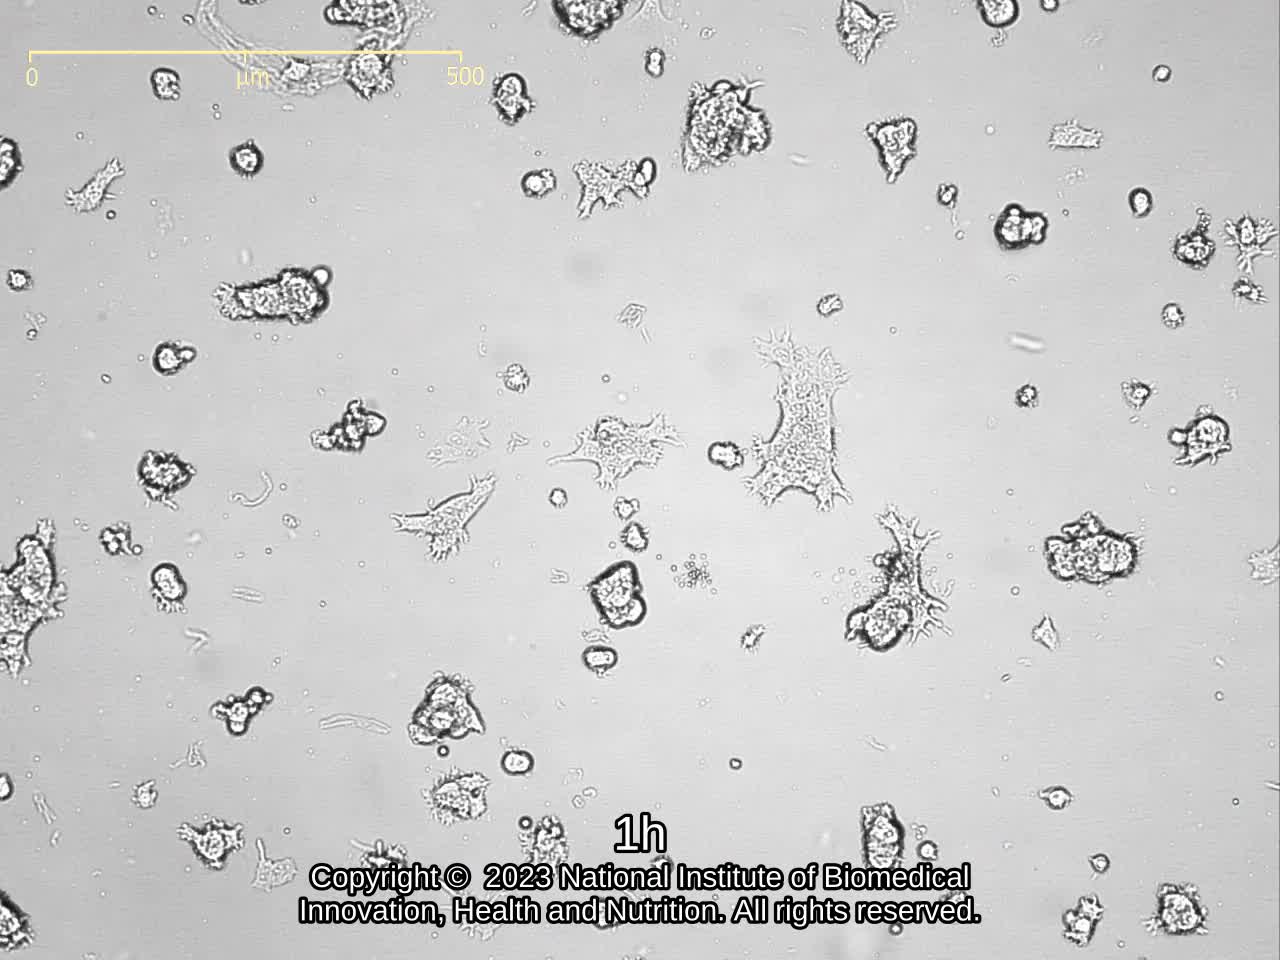

| Images |

![]() ![]() ![]() ![]() ![]() ![]() ![]() ![]() |

| Movies |

|